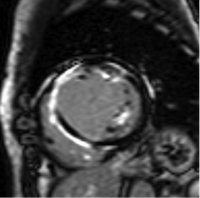

前壁中隔心筋梗塞症例)黒く描出された正常心筋に対し、 前壁中隔内膜側に遅延造影像を認め、心筋梗塞による障害心筋の評価が可能です。